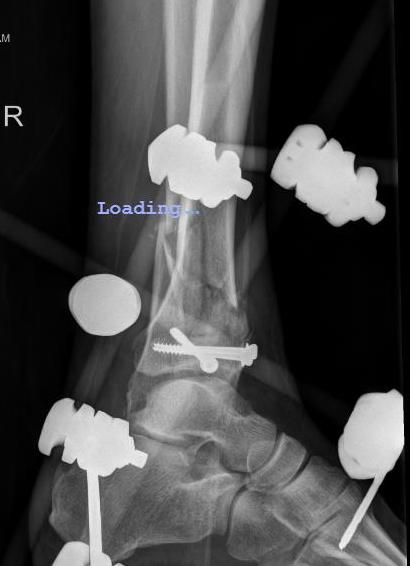

Technique of ankle bridging delta frame

- two pins in the tibia away from surgical site

- transcalcaneal threaded pin placed medial to lateral

- pin in base of first metatarsal to keep foot in neutral position and prevent equinus contracture

- note: pin in base of first metatarsal places deep plantar branch of dorsalis pedis at risk